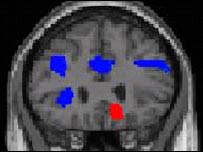

تصوير مغز

در افراد افسرده برخی نواحی مغز فعالتر و برخی نواحی مغز خموده تر است